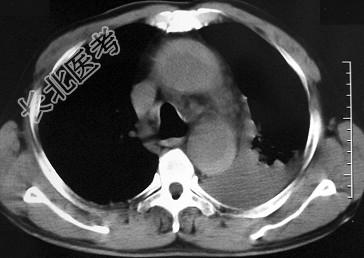

- 单项选择题男,58岁, 有高血压病史,突发胸背剧痛, CT扫描如图,其最可能的诊断为 ( )

A、主动脉瘤

B、主动脉假性动脉瘤

C、主动脉窦瘤破裂

D、高安病

E、主动脉夹层动脉瘤